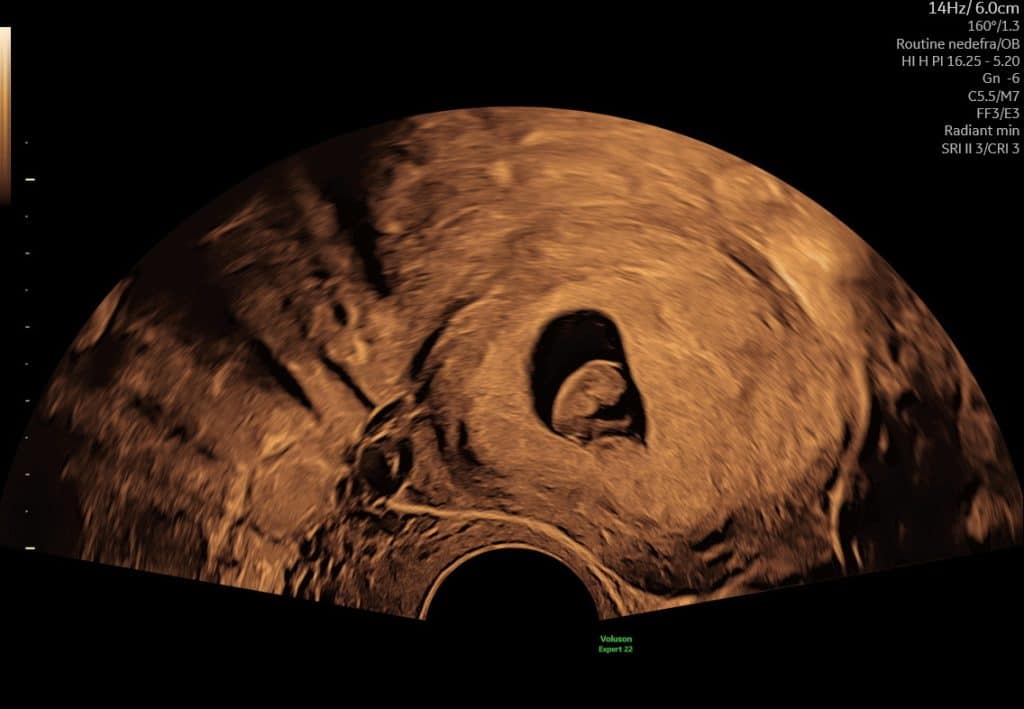

Ultralydsscanning uge 7 hjerteblink

Ultralydsscanning uge 8 lille foster i livmoderen

Eksempel på ultralyd i uge 7–8. Hjerteblink kan ofte ses, men synligheden varierer.

I denne periode kan bevægelse ofte ses tydeligere på video end på stillbilleder.

Kort ultralydssekvens fra uge 7, hvor hjerteaktivitet og tidlig bevægelse kan ses